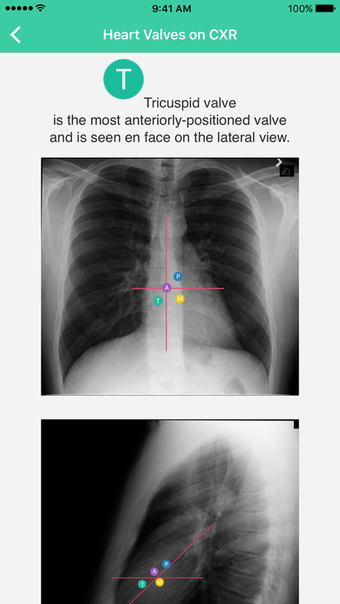

Radiology Toolbox Proadalah aplikasi versi lengkap untuk iPhone, termasuk dalam kategori 'Kedokteran' .

Radiology Toolbox Pro tersedia untuk iOS 12.1.2 atau lebih tinggi. Versi program saat ini adalah 3.0.03, dan Anda hanya dapat menjalankannya dalam bahasa Inggris.